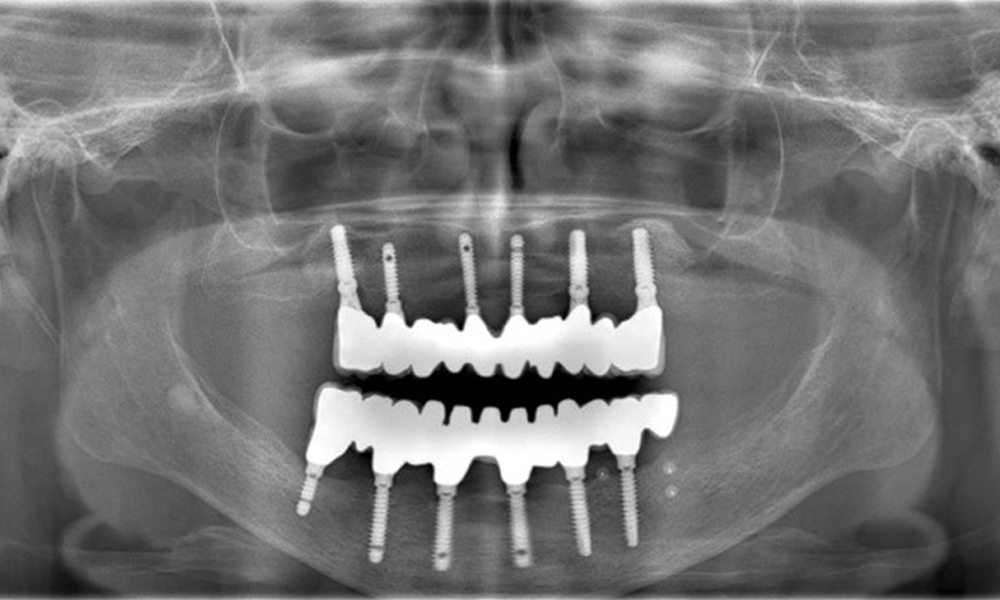

Eine 74-jährige Patientin stellt sich in der Sprechstunde vor. Die Anamnese zeigt, dass die Patientin gut eingestellten Bluthochdruck hat und Lixiana einnimmt. Weiterhin hatte die Patientin im Jahr 2020 ein Nierenkarzinom. Die Lebensgewohnheiten der Patientin sind unauffällig. Die Patientin hat keine eigenen Zähne mehr. Sie hat im Oberkiefer und Unterkiefer jeweils sechs Implantate, die mit Kronen bzw. über Brücken versorgt sind. Anhand der aktuellen Befunde lässt sich keine periimplantäre Mukositis bzw. Periimplantitis feststellen; vereinzelte (geringfügige) Blutungen an den Implantat(-versorgungen) liegen vor.

Versorgungen: Implantate regio 011, 013, 015, 021, 023, 025, 031, 033, 035, 042, 044, 046

Die Röntgenaufnahmen zeigen den Knochenabbau.

Abb. 2: Die Röntgenaufnahmen zeigen den Knochenabbau.